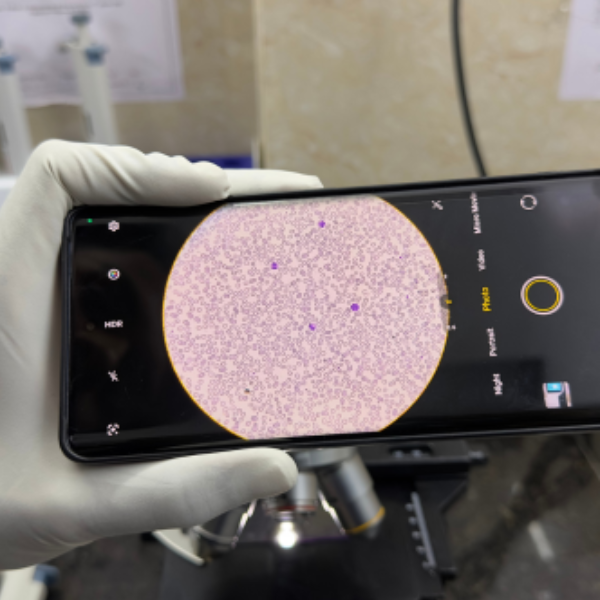

01. Routine and Specialized Blood Tests

Comprehensive blood testing for infections, metabolic disorders, organ function, and overall health assessment.

03. Biochemistry, Hematology, and Serology Testing

Advanced testing services to evaluate immune response, blood disorders, and biochemical imbalances with high accuracy.